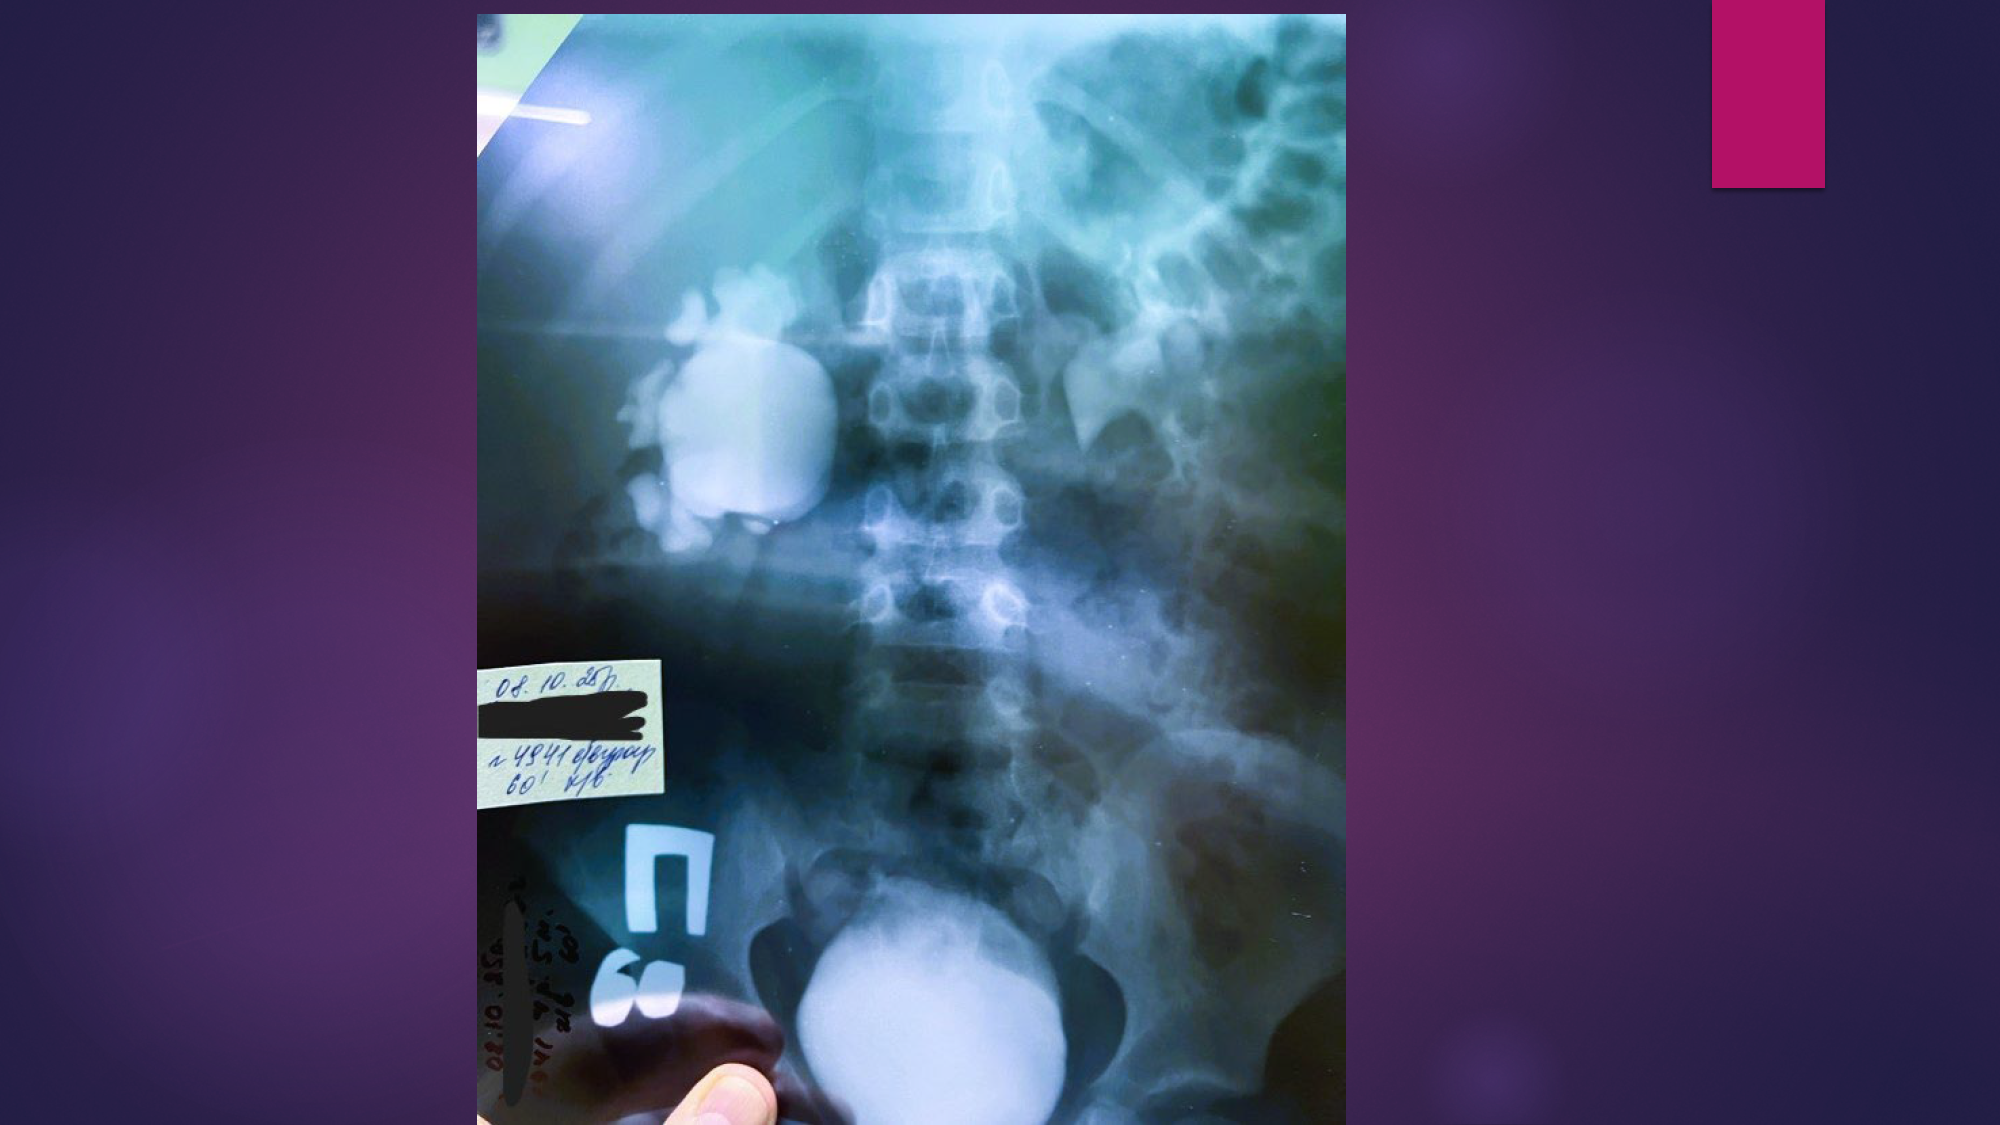

Хлопчик Ю., 4роки, гідронефроз 3 стадії справа